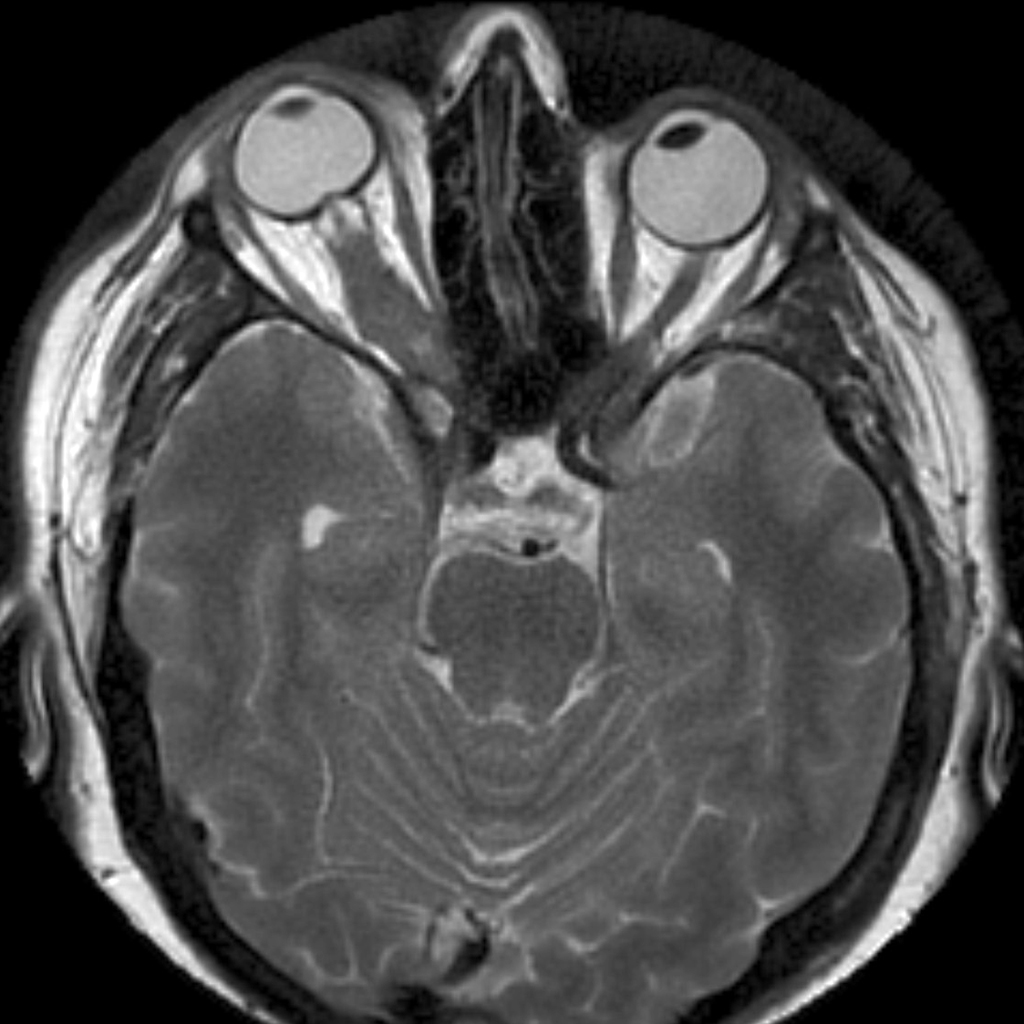

Патогномоничным признаком глиомы зрительного нерва долгие годы считали расширение кольца его костного канала, выявляемого при рентгенологическом исследовании. КТ позволяет не только визуально наблюдать веретенообразно или цилиндрически увеличенный зрительный нерв в орбите, но и судить о его распространении по зрительному каналу в полость черепа. Ультразвуковое сканирование недостаточно информативно, так как представляет изображение только проксимальной и средней трети зрительного нерва. МРТ более информативно при интракраниальном распространении опухоли.

- МРТ головного мозга и орбиты

- КТ головного мозга и орбиты